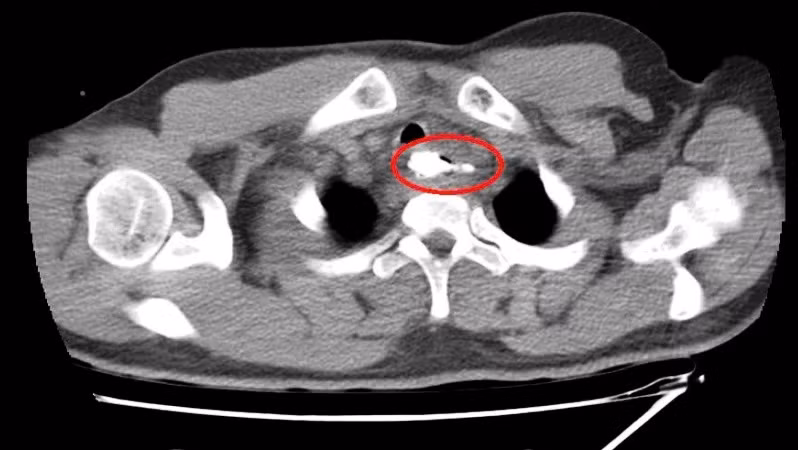

Qua thăm khám lâm sàng, chụp cắt lớp vi tính vùng cổ, nội soi mềm thực quản, các bác sĩ phát hiện một dị vật là mẩu xương lớn, nằm ở thực quản đoạn ngực có khả năng gây thủng thực quản, tổn thương nghiêm trọng đến các cơ quan xung quanh.

Ngay lập tức, bệnh nhân được chuyển đến phòng mổ để tiến hành nội soi thực quản ống cứng lấy dị vật dưới gây mê. Quá trình phẫu thuật kéo dài hơn một giờ, đội ngũ nhân viên y tế của các chuyên khoa: Ngoại Nhi Cấp cứu bụng, Tai Mũi Họng, Gây mê hồi sức tại Bệnh viện Trung ương Huế phối hợp thực hiện, khéo léo lấy bỏ dị vật mà không làm tổn hại thêm đến thực quản. Dị vật là mẩu xương heo, có mấu nhọn, kích thước 30x41mm, nằm ở thực quản đoạn ngực, cách cung răng trên 20cm.

| Dị vật là mẩu xương heo, có mấu nhọn, kích thước 30x41mm, nằm ở thực quản đoạn ngực, cách cung răng trên 20cm. |